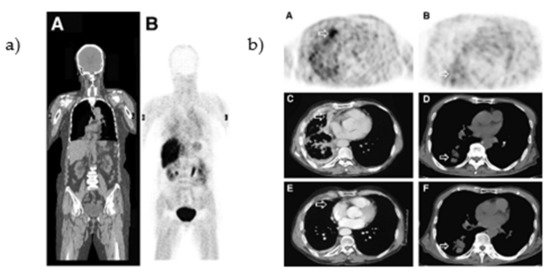

- Weber, B.; Winterdahl, M.; Memon, A.; Sorensen, B.S.; Keiding, S.; Sorensen, L.; Nexo, E.; Meldgaard, P. Erlotinib Accumulation in Brain Metastases from Non-small Cell Lung Cancer: Visualization by Positron Emission Tomography in a Patient Harboring a Mutation in the Epidermal Growth Factor Receptor. J. Thorac. Oncol. 2011, 6, 1287–1289. [Google Scholar] [CrossRef]